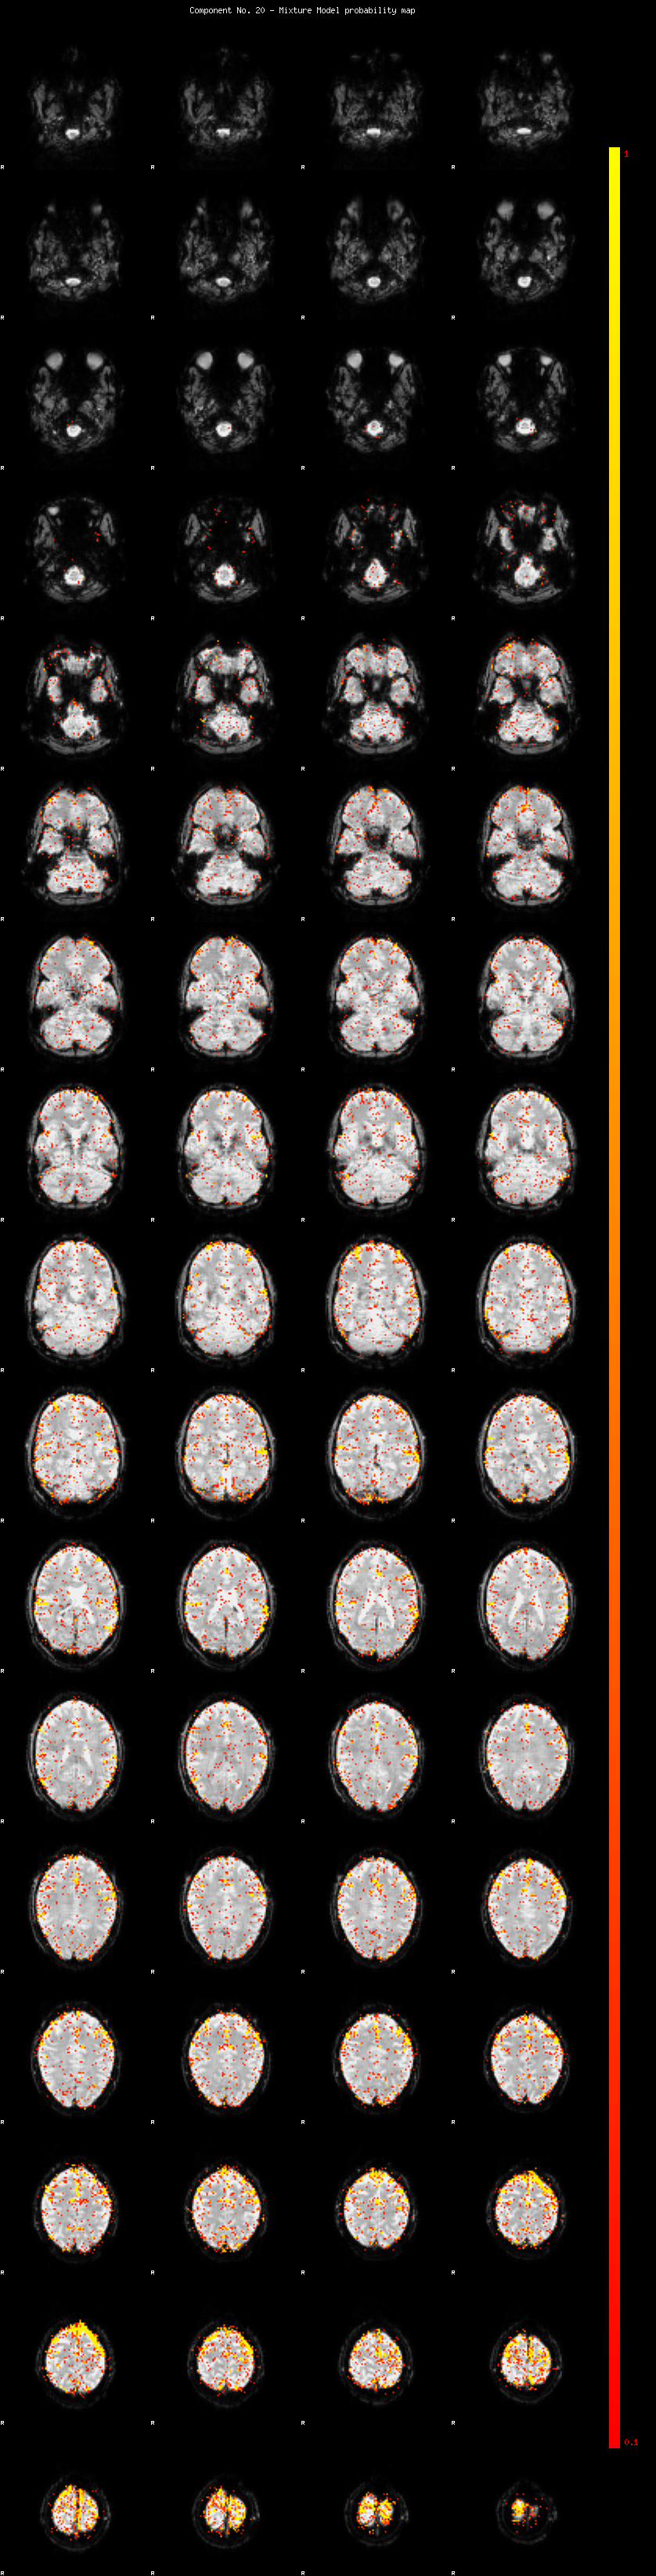

IC_20 Mixture Model fit

Means : -0.000000 3.331853 -2.816083

Vars : 1.000000 5.171210 0.606418

Prop. : 0.949612 0.041476 0.008911